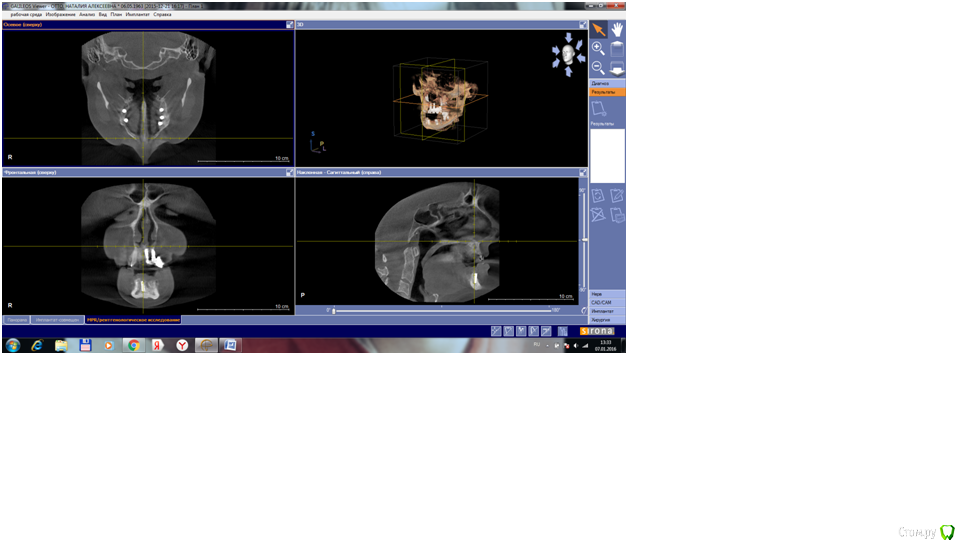

Nataly07 Опубликовано 7 января, 2016 Поделиться Опубликовано 7 января, 2016 Уважаемые доктора, была бы очень благодарна вам, если бы нашли время ответить на очень важный для меня вопрос. В начале декабря 2015 была проведена операция по имплантации на нижней челюсти. Были установлены 5 имплантатов. После операции выяснилось, что с левой стороны присутствует онемение подбородка. Была сделана КТ. Хирург посмотрел снимок и сказал, что всё нормально, имплантат не касается нерва. В заключении врача-рентгенолога написано: имплантат 3.5 – апикальная треть перфорирует нижнечелюстной канал на всем протяжении в области ментального отверстия. Ниже имплантата с оральной стороны визуализируется дефект оральной компактной пластинки. В переводе с медицинского на общечеловеческий язык, что это означает и каковы должны быть дальнейшие действия?Имплантат 4.3 – ниже имплантата визуализируется сквозной дефект нижней компактной пластинки. Имплантат надо удалять? Какие могут быть последствия, если его не удалять?Снимки сделаны в программе Галилео, не знаю, как их сохранить. Ссылка на комментарий

Nataly07 Опубликовано 8 января, 2016 Автор Поделиться Опубликовано 8 января, 2016 Да, онемение есть в левой части подбородка Ссылка на комментарий

Nataly07 Опубликовано 8 января, 2016 Автор Поделиться Опубликовано 8 января, 2016 1 Ссылка на комментарий